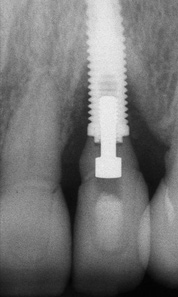

Some amount of microleakage can be expected with any current implant-abutment interface.23,24 External hexagon implants have been found to fail to prevent microleakage.23 Figure 3 and Figure 4 depict an external hexagon implant with an implant-abutment connection vulnerable to microleakage. This same study found internal hexagon implants with internal conical (Morse taper) connection to have the least amount of leakage. Zirconia abutments were found to have more microleakage than titanium abutments. As a result, this study recommended restricting the use of zirconia abutments to cases where esthetic demands are high.23

Fig 3. Clinical and radiographic views of an external hexagon implant restored using a zirconia abutment. The radiograph indicates an implant–abutment connection vulnerable to microleakage. Severe bone loss was due to peri-implantitis.

Figure 3

Fig 4. Clinical and radiographic views of an external hexagon implant restored using a zirconia abutment. The radiograph indicates an implant–abutment connection vulnerable to microleakage. Severe bone loss was due to peri-implantitis.

Figure 4